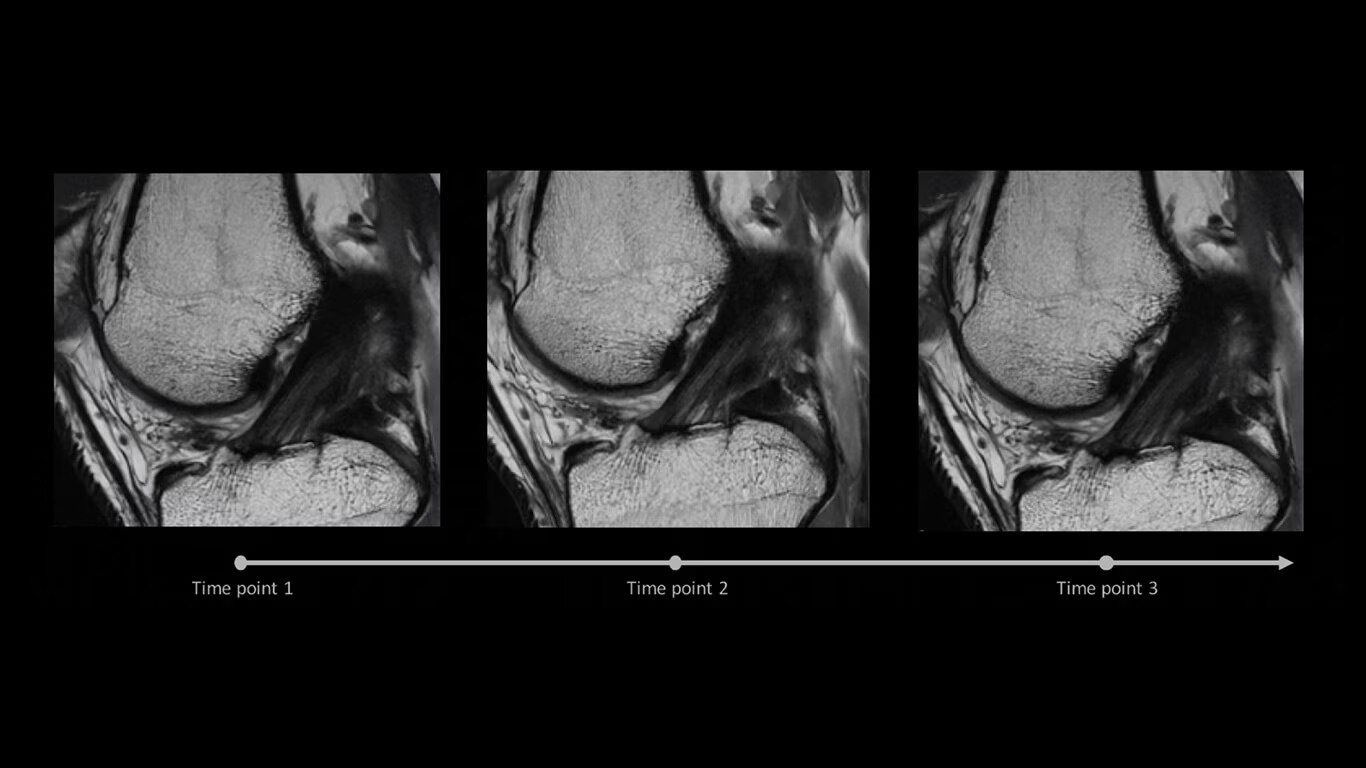

AIR x™ automatically detects patient anatomy and prescribes MRI slices for routine and challenging neurological and knee exams, delivering consistent and quantifiable results.

Deliver consistent MRI slice placements across multiple clinical time points, with a deep-learning algorithm that provides efficiency and time savings.

Reduce the need for rescans with AIR x™, which automatically detects anatomies and determines the best position for MRI slices.